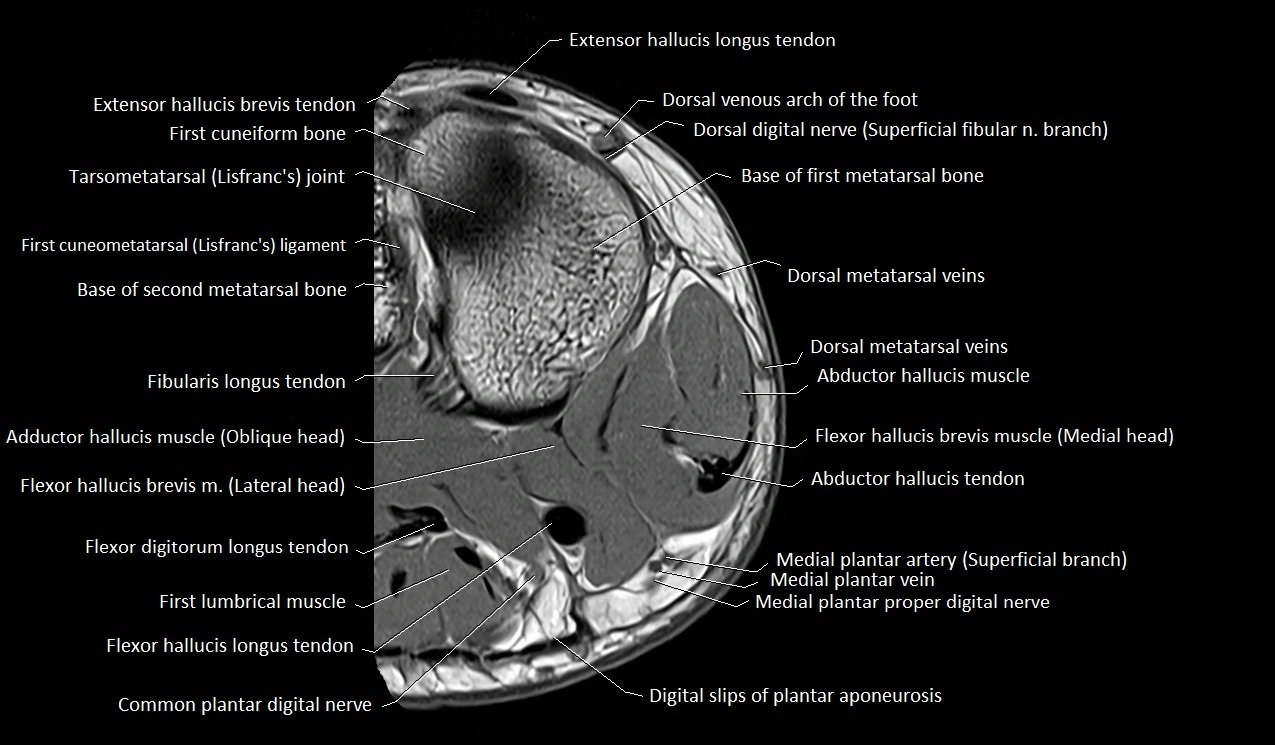

MRI image

image